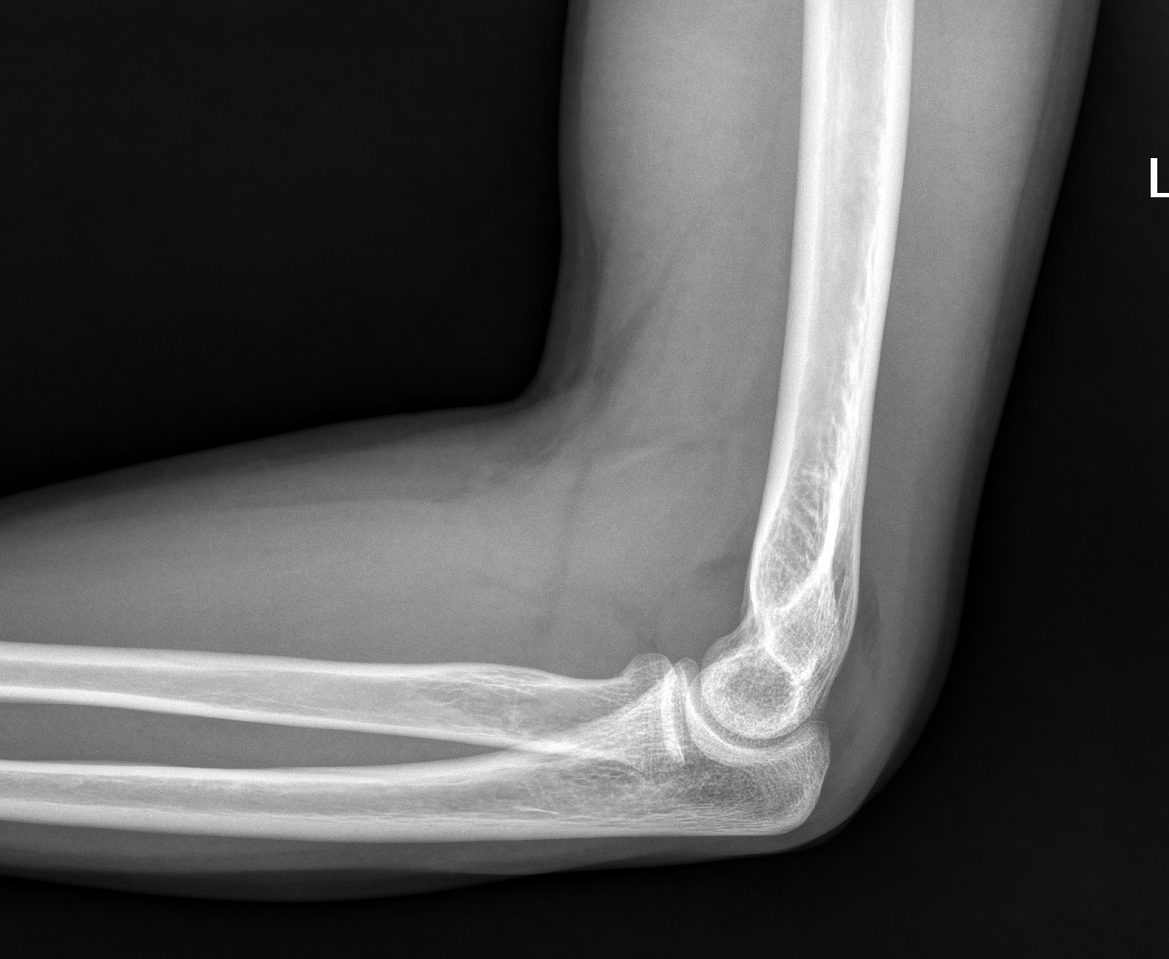

James Heilman, MD - Own work, CC BY-SA 4.0, Link

Non ou peu déplacée (I et II) : vérifier cliniquement s’il existe un blocage en prono-supination.

Si absence de blocage mécanique (même si douleur), traitement fonctionnel avec coude au corps 48 heures puis mobilisation libre. Consultation à J7.

« Equivalent » d’une fracture = signe de la voile. Traitement fonctionnel avec coude au corps 48 heures puis mobilisation libre. Consultation orthopédique à J7.

Déplacée ou avec blocage : avis chirurgical.